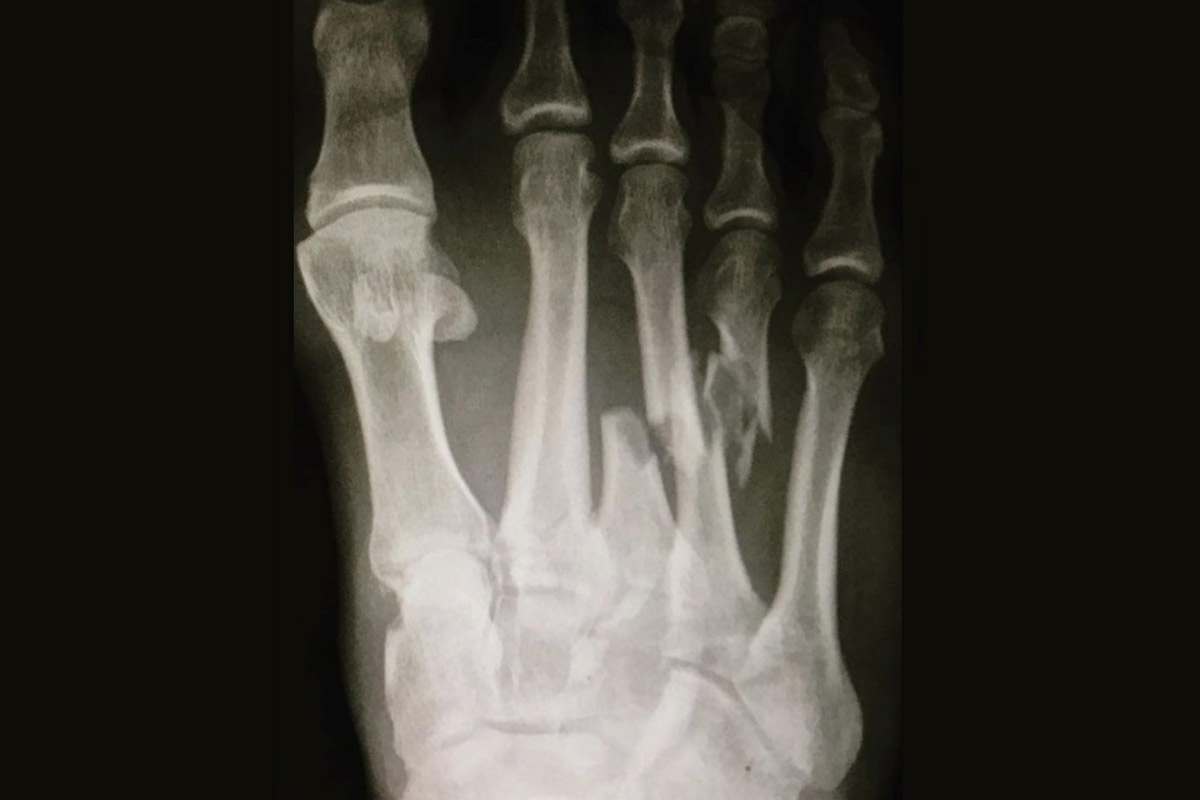

To an untrained eye, it may have looked as if he only fractured two bones in the middle of his foot. If those bones (known as the 3rd and 4th metatarsal shafts) were injured alone, Slater could have potentially been back on his board in six to eight weeks.

Instead, he also injured the bones and ligaments involving the 1st and 2nd metatarsal-cuneiform joints of the Lisfranc (or midfoot) joint.

There are actually multiple joints in the Lisfranc joint, with five metatarsal bones, three cuneiform bones and a cuboid bone.

There also is a strong ligament connecting the medial cuneiform and 2nd metatarsal base called the Lisfranc ligament.

When the Lisfranc ligament and other ligaments of the Lisfranc joint are injured, the bones of this joint become unstable. This instability, even with just millimeters of displacement, can cause severe pain, and will lead to arthritis and an even more painful foot with deformity if not treated surgically.

In Slater’s situation, he needed an open reduction and internal fixation (ORIF) of the Lisfranc joint as well as the 3rd and 4th metatarsals. Because the plate is used to temporarily hold the bones of the Lisfranc joint in place while the ligaments heal, it is actually critical to remove the trapezoidal-looking plate so the joint can function properly.